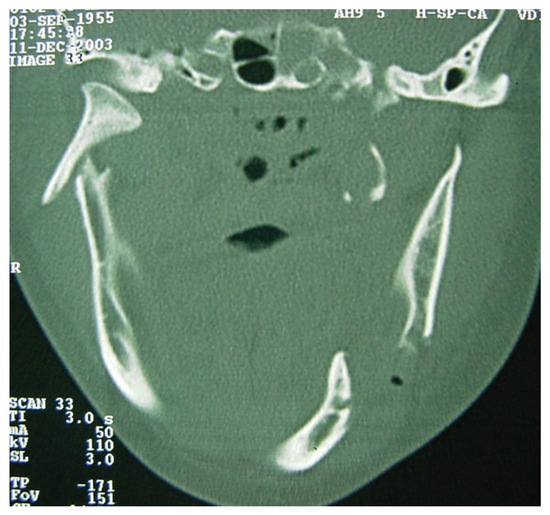

A computed tomography (CT) was performed in a fourchannel spiral CT scanner (Toshiba Asteion 4; Toshiba, Tokyo, Japan) with axial, coronal, and sagittal views. Multiple frac-tures were identified on the face (Figure 2 and Figure 3) and on the left side of the SS region (Figure 4).

Figure 4.

CT windows with arrows highlighting fractures to the sphenoidal sinus.